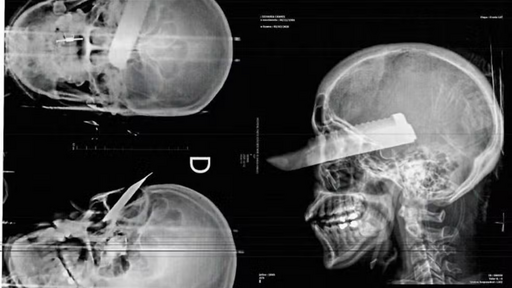

Foto: PMSC/ Divulgação - Mulher é gravemente ferida no olho durante tentativa de feminicídio no Oeste de SC

Segundo as autoridades, a vítima foi agredida dentro da própria residência e atingida por um golpe de faca no rosto, que causou uma lesão grave no olho direito. Mesmo ferida, a mulher conseguiu fugir do local, pediu ajuda a vizinhos e foi atendida pelo Corpo de Bombeiros.